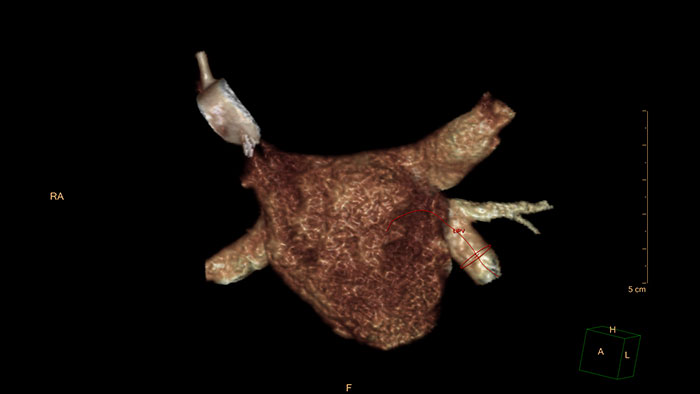

CT imaging in TAVI to advance patient care

Provides 2D and 3D visualization and automated measurements designed to assist in proper TAVI-device sizing, on contrast-enhanced, prospectively ECG-gated axial or retrospectively gated helical CT images.